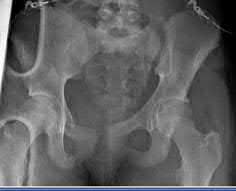

Question 10:

A hemodynamically unstable 42-year-old male is brought to the trauma bay after a motorcycle crash. Pelvic radiographs demonstrate an APC-III pelvic ring injury ('open book' pelvis). A pelvic binder is immediately applied by the trauma team. Which of the following statements regarding the application and function of a pelvic binder is most accurate?

Correct Answer: It must be centered exactly over the greater trochanters to effectively close the pelvic ring

Explanation:

To be effective in reducing pelvic volume and closing an open-book pelvic injury, a pelvic binder (or sheet) must be centered low, directly over the greater trochanters. Positioning it too high over the iliac crests can actually worsen the deformity by acting as a fulcrum. Its primary mechanism of action is reducing pelvic volume to encourage tamponade of the massive venous plexus bleeding, not arterial bleeding.